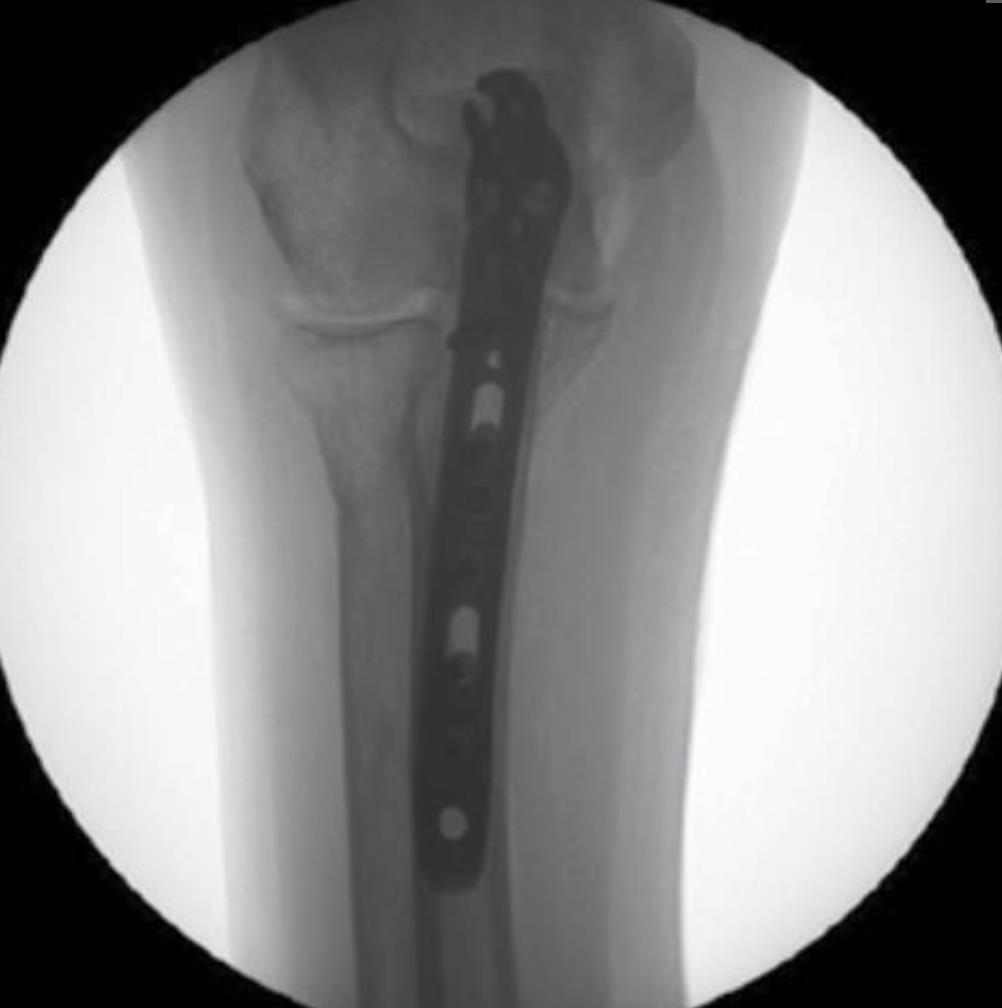

• Plate Selection

• select the appropriate length of plate that provides at least six cortices of fixation distal to the fracture line

• Provisional Plate Fixation

• apply the plate to the proximal fragment confirming that the plate is centered on the ulna shaft and that the HR tab is flush to the olecranon

• secure the plate to the proximal fragment using a 2mm K-Wire through the hole at the base of the HR tab

• Fracture Reduction

• reduce the fracture by levering the shaft of the plate to the distal fragment

• confirm fracture reduction and plate alignment using fluoroscopy

• Distal Fragment Fixation

• using the 2.7mm x 40mm drill bit, drill through the distal end of a FreeFix slot that is distal to the fracture line through both cortices

• this will allow for dynamic compression of the fracture

• measure screw length using the appropriate scale on the 50mm Depth Gauge, then insert a 3.5mm compression screw using the T-10 Driver while applying interfragmentary compression